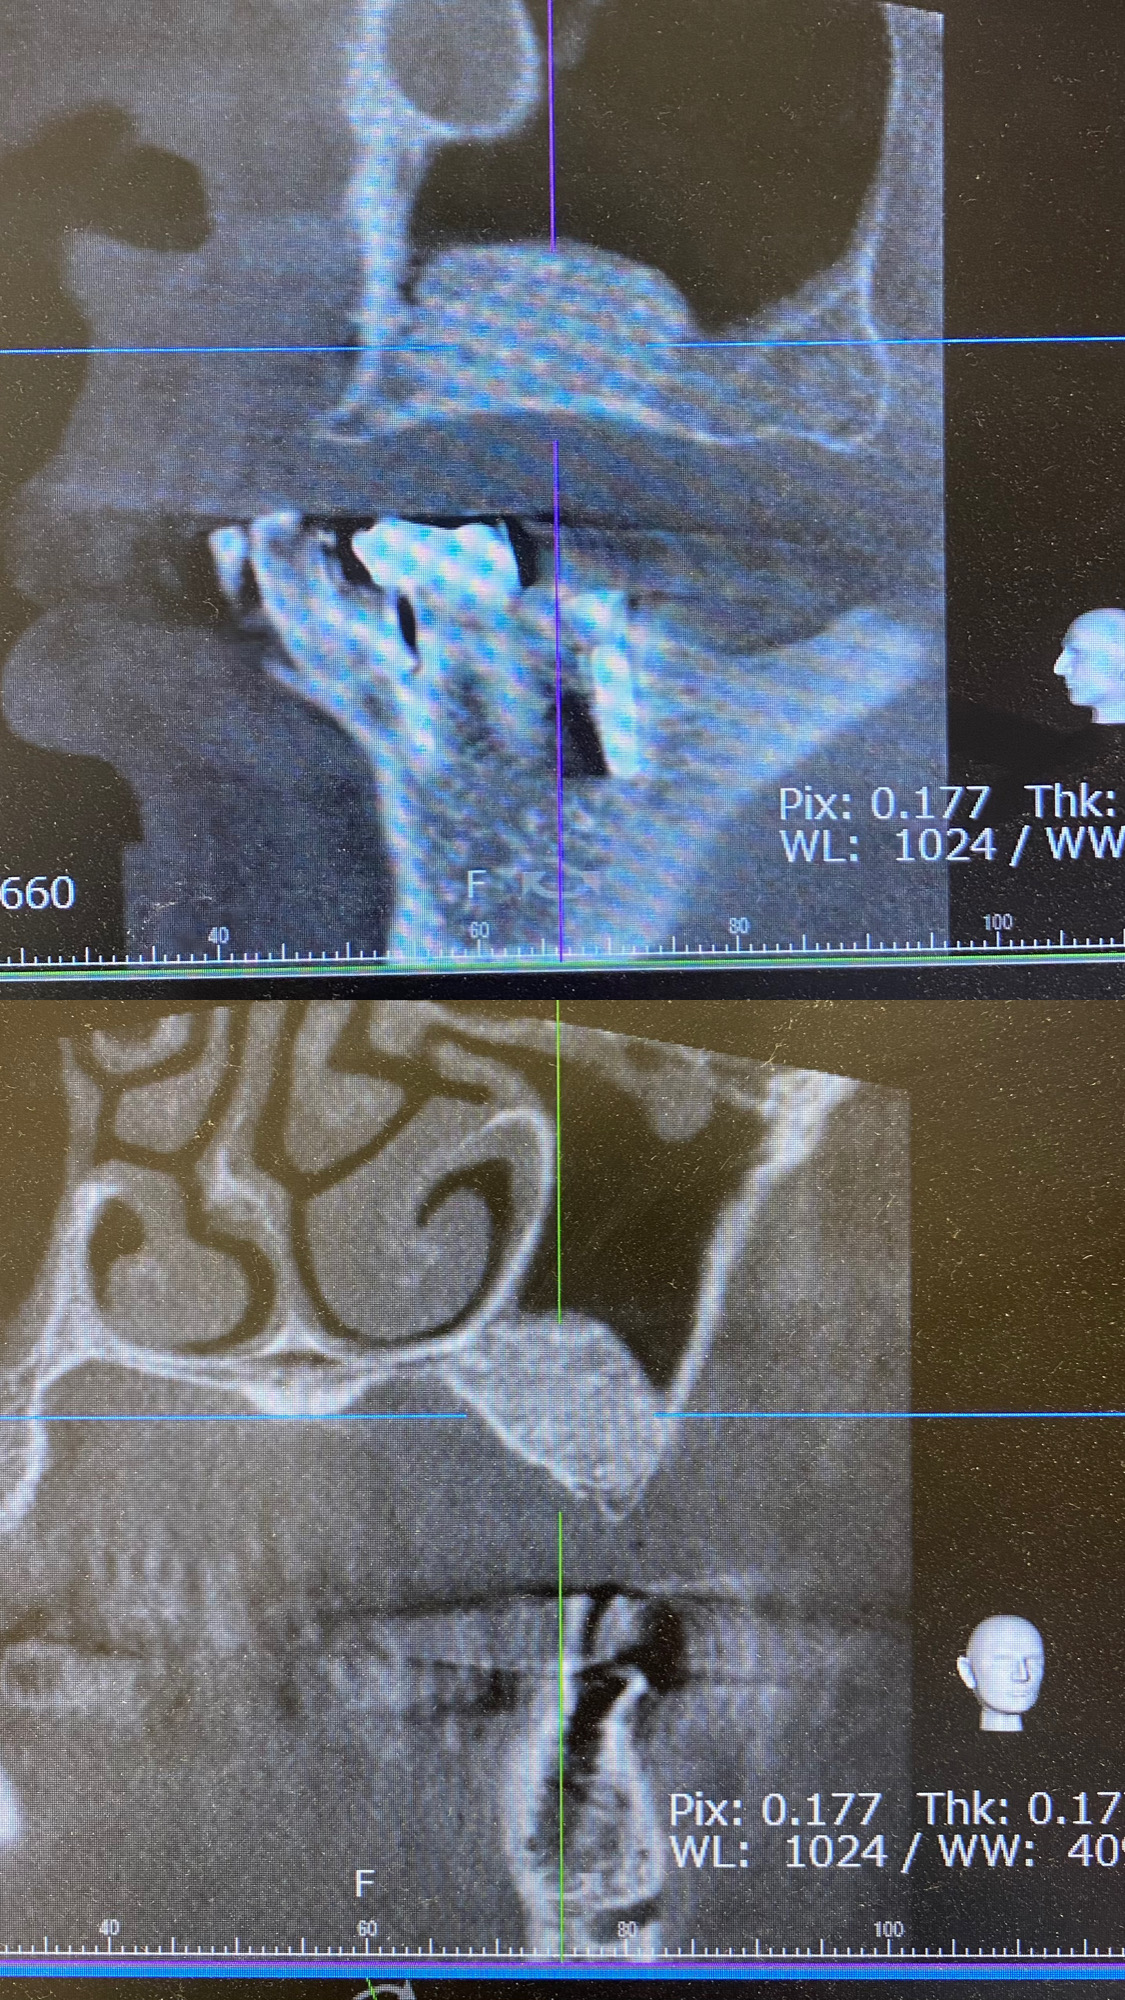

1枚目の写真 GBR前後

2枚目の写真 サイナスリフト後

写真は全て当院で行なった症例です。

①サイナスリフト

上顎奥歯の骨が大幅に不足している場合、上顎洞に骨を増やす手術。

インプラントを同時に埋入できない場合もあります。

③GBR

上顎、下顎共に垂直、水平的に骨がない場合チタンメッシュ、またはコラーゲン膜を用いて骨を増やす手術。

広範囲で行う場合はインプラントを同時に埋入できない場合もあります。